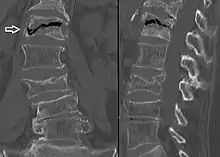

| Example of vertebral compression fracture. | |

Compression fracture of the fourth lumbar vertebra post falling from a height.